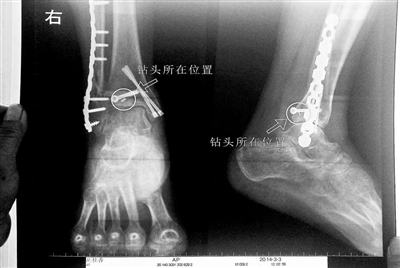

胡女士的腿部X光圖

看著X光片中自己腿內(nèi)的異物,胡女士就感到莫名的擔(dān)憂。胡女士于2013年3月在北京市豐臺區(qū)右安門醫(yī)院進(jìn)行了一次骨折手術(shù),術(shù)后醫(yī)生才發(fā)現(xiàn)手術(shù)時用來打眼用的鉆頭不慎遺留在了胡女士的骨頭中,并且無法取出。

近日,在豐臺區(qū)右安門醫(yī)院,北京青年報記者見到了胡女士,她走起路來顯得一瘸一拐,腿腳并不利索。在她帶來的X光片上,可以清晰地看到,有一個異物存在于腿內(nèi)部。

“我當(dāng)時就嚇蒙了,怎么會有一個鉆頭在骨頭里?”胡女士余悸未消地說,第二天拍攝的X光片顯示,2厘米左右的鉆頭遺留在她右腳腳踝上部的骨頭內(nèi)。

胡女士說,當(dāng)時旁邊的醫(yī)生勸慰自己,稱鉆頭留在腿里并不會有什么問題。出院后,胡女士每個月都會來醫(yī)院做復(fù)查,拍X光片。她說,每次都能夠清晰地看見自己骨頭里的那個明晃晃的“小東西”。